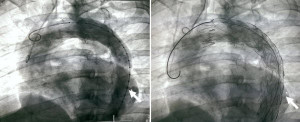

Các bác sĩ Bệnh viện Hữu Nghị Việt Đức vừa cứu sống một bệnh nhân bị chấn thương eo động mạch chủ hiếm gặp...